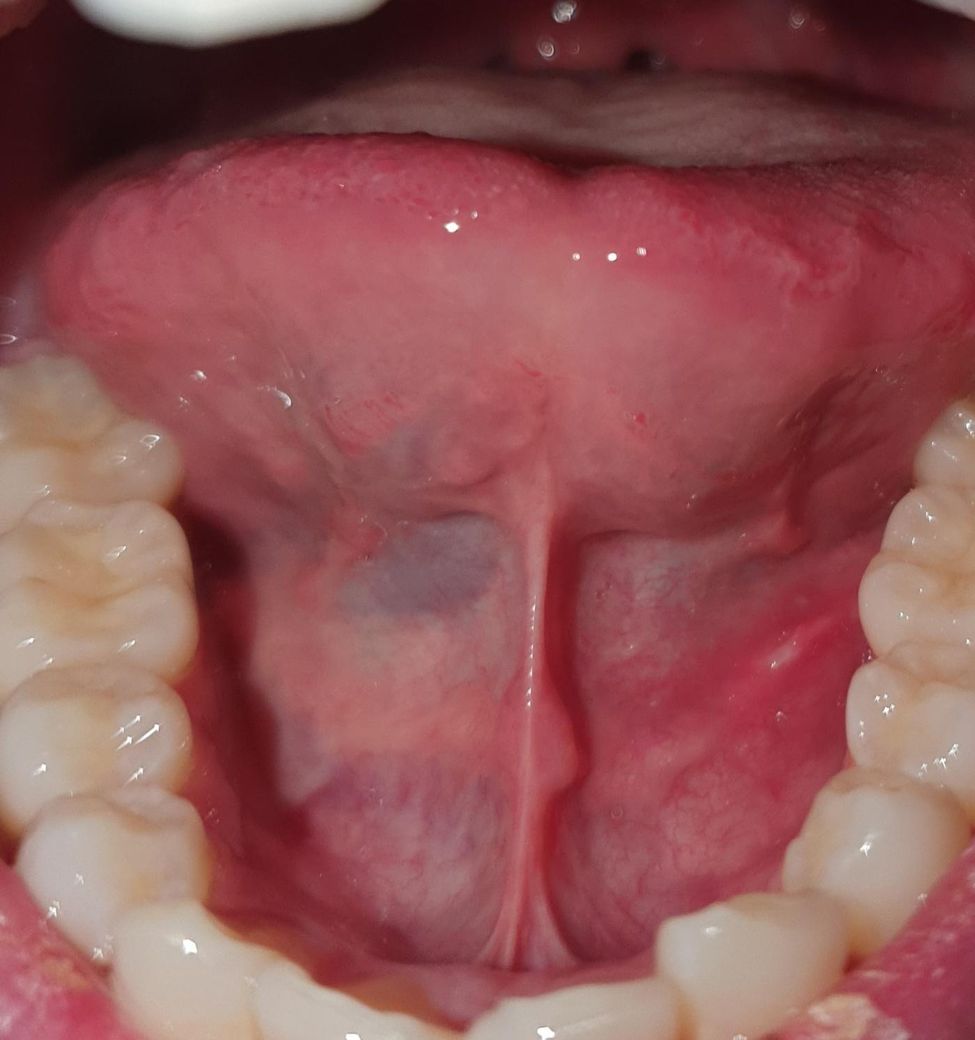

혀 밑에 힘줄? 구강저에 통증이 있는 것 같아요. 이유가 뭘까요

혀 밑 힘줄 부분? 그 옆부분이라 해야하나

그 주위에 불편감? 통증?이 느껴져요.

사진 찍어보니까

아픈 부위가 저렇게 노랗게 돼버렸는데 이유가 뭘까요?

사진 상으로는 특별히 문제가 보이진 않습니다. 일시적인 자극에 의한 것 일수도 있습니다.

혀 밑 조직이 자극을 받아서 그럴수 있습니다. 최대한 자극이 가지 않도록 하면 시간이 지나면 괜찮아 지실꺼에요.

점막조직에 자극이 되거나 한다면 불편감이 생길수 있습니다. 사진으로는 크게 문제가 보이지는 않습니다 불편감이 있다면 자세한 확인을 위해서 치과에서 진료를 받아보는 것을 권유드립니다.